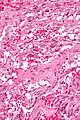

A gangliocytic paraganglioma is a rare tumour that is typically found in the duodenum and consists of three components: (1) ganglion cells, (2) epithelioid cells (paraganglioma-like) and, (3) spindle cells (schwannoma-like).[1]

GP consist of three components (1) ganglion cells, (2) epithelioid cells (neuroendocrine-like), and (3) spindle cells (schwannoma-like). The microscopic differential diagnosis includes poorly differentiated carcinoma, neuroendocrine tumour and paraganglioma.[1]

Intermed. mag.

Intermed. mag. Intermed. mag.